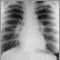

Sarcoidosis is a disease of unknown cause in which inflammation occurs in the lymph nodes, lungs, liver, eyes, skin, or other tissues.

The cause of the disease is unknown. Sarcoidosis is marked by abnormal inflammatory masses (granulomas) in certain organs of the body. Granulomas are clusters of immune cells (macrophages, lymphocytes, and multinucleated giant cells). The disease can affect almost any organ of the body, although it most commonly affects the lungs. Sarcoidosis can be acute, subacute, or chronic.

Note: There may be no symptoms. Most of the time, the disease is found in patients with no symptoms who have an abnormal chest x-ray.